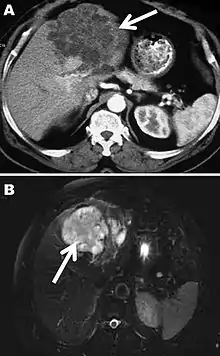

Polycystic echinococcosis affecting the left side of the liver

The diagnosis of polycystic echinococcosis involves isolating the protoscoleces during surgery or after the patients death in order to identify E. vogeli. Imaging, such as ultrasound and CT scans, can also be used to identify polystytic structures, but this method is not preferred as images are similar to other types of echinococcosis and liver cancer. New studies show that PCR may identify E. vogeli in the patients tissues.[5]

Polycystic echinococcosis (PE) is an extremely lethal helminthic disease in humans, which is caused by the larval form of E. vogeli. Type I PE consists of polycystic masses in the liver and abdominal cavity. Type II also has polcystic masses in the liver and abdominal cavity, but includes hepatic insufficiency. Type III has polcystic masses in the liver and chest cavity. In type IV polycystic masses occur only in the mesenteries. Type V has calcified cysts in the liver and lung.[4] Type II seems to have the highest mortality rate due to the complications involved with hepatic insufficiency. Due to the similarities between liver cancer and polycystic echinococcosis, PE is hard to diagnose and could deadly when metastasized to other organs.